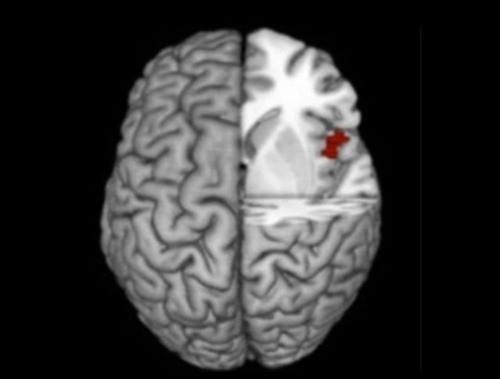

자기 희생적 행위와 전두엽.jpg

이탈리아 국제과학연구대학원(SISSA)과 볼로냐대학, 미국 하버드대학 등 공동연구팀은 80명을 대상으로 가상현실(VR) 환경을 이용해 불타는 건물에서 빨리 탈출해야 하는 상황을 만들어 행동과 심리변화를 관찰했다. 이 실험 도중 기능성 자기공명영상장치(fMRI)로 촬영한 결과 위험을 무릅쓰고 타인을 구하는 행동을 하는 동안 이들의 '전두엽 오른쪽 섬엽'(right anterior insula)이라는 뇌 부위가 활성화되며 커진 것으로 나타났다. 호두알 크기 정도인 이 부위는 공감적 관심이나 타인의 감정을 읽고 이해하는 능력을 포함한 사회적 감정이나 도덕적 정보처리 능력과 관계 있는 것으로 알려져 있다. (연합뉴스 2017. 3.14)